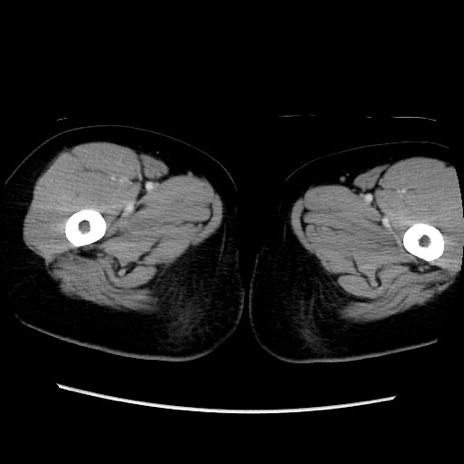

症例39(横断像)

【症例】40歳代女性

【主訴】上下腹部痛

【現病歴】2日目から下腹部痛あり。夜間は痛みで眠れなかった。昨日より上腹部痛と下痢が出現。臥位で痛みは軽快したため、休んでいた。本日になって臥位でも立位でも痛みが強くなってきたため救急要請。

【既往歴】子宮内膜症

【身体所見】部:平坦・軟、左上下腹部に圧痛あり、反跳痛あり。

【データ】WBC 21800、CRP 26.78